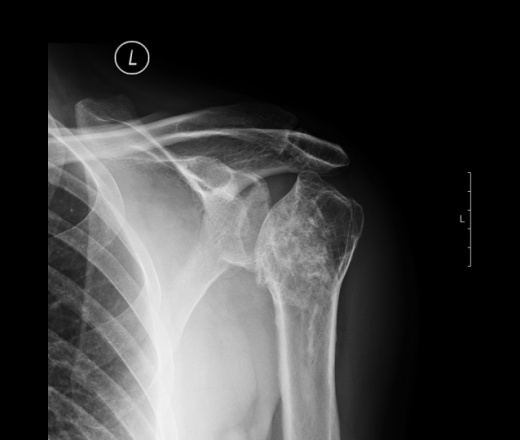

Для диагностики заболевания специалист проводит осмотр пациента и выявляет признаки повреждения головки плечевого сустава. На ранних стадиях болезни рентгенография не дает достаточной информации, но на более поздних становится более информативной. Этот метод позволяет обнаружить изменения в форме головки плечевой кости, размытые контуры, неоднородную текстуру и расширенные суставные щели.

С помощью компьютерной томографии (КТ) или магнитно-резонансной томографии (МРТ) врач может выявить начальные стадии патологического процесса в костной ткани. Анализы крови помогают определить наличие воспалительных процессов в организме.